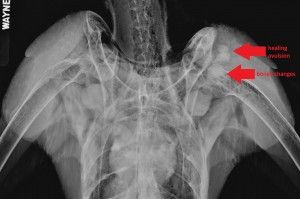

LATEST UPDATE ON NX December 20 update NX was anesthetized this morning for another set of radiographs. Dr. Miranda reports that the coracoid avulsion is healing. It’s too soon to tell if the piece of bone is re-attaching or if it will be reabsorbed, as the healing is still taking place. An additional development: radiographs also revealed boney changes taking place on the head of NX’s left humerus. At this point, it’s too soon to tell what that may mean – it could be possible joint involvement with her shoulder injury, or it could just be another stage of healing. Only time will tell as the coracoid fracture heals. Dr. Miranda is happy with NX’s range of motion in this wing, meaning that Dr. Miranda can’t feel any sort of major issues in the shoulder. ![]() NX will remain indoors in a body wrap for one more week. After that, the wrap will be taken off and the veterinary team will monitor her. Radiographs will be taken again during the first week of January. |